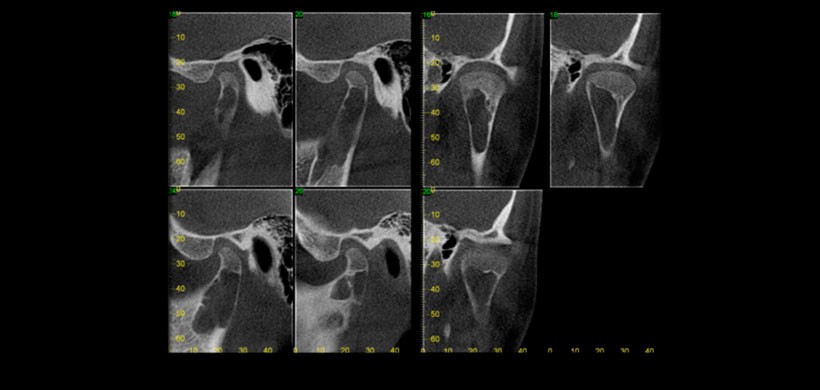

Figura 2: Tomografía volumétrica de haz cónico